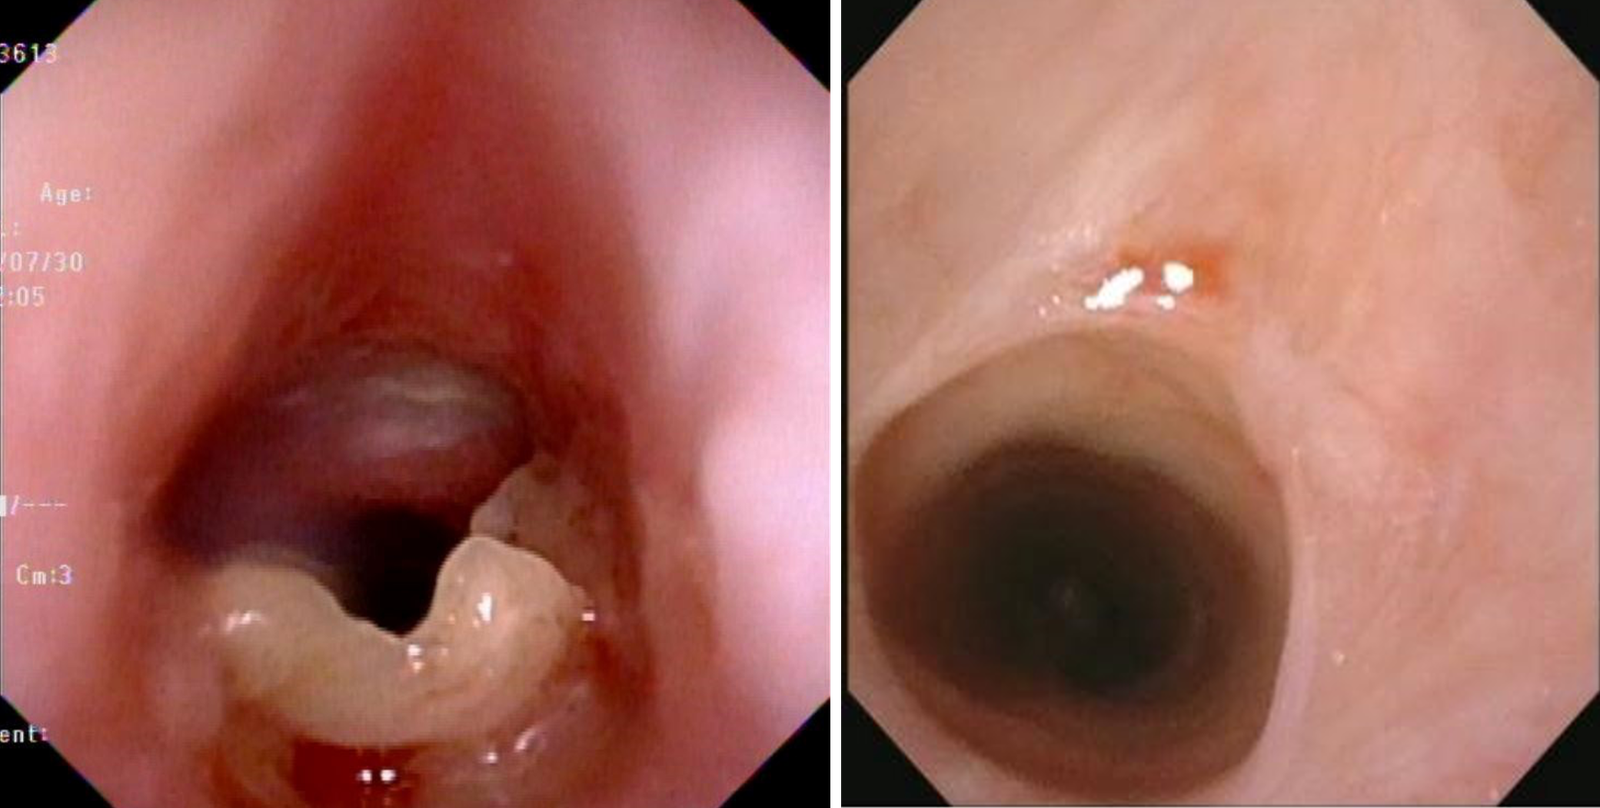

During the procedure, a significant narrowing of the subglottic airway was visualized, approximately 2 mm below the vocal cords. The stenotic lesion was noted to be fibrotic, with an estimated Grade II stenosis based on the Cotton-Myer grading system (Figure 1), obstructing approximately 70% of the airway lumen. The vocal cords had normal mobility and appearance.

Based on the bronchoscopic findings and the patient's clinical symptoms, it was decided to proceed with an immediate therapeutic intervention during the same session. Utilizing the flexible bronchoscope, a Diode laser was advanced through the working channel with the bronchoscope. During laser ablation, the high flow nasal cannula settings, especially FiO2 was reduced to 30% to minimize the risk of airway fire. The contact Diode laser with power of 5w in continuous mode was used to precisely ablate the fibrotic scar tissue, systematically vaporizing the stenotic ring. Care was taken to avoid a full-thickness ablation and to protect the cricoid cartilage. Following the laser ablation, the airway was re-examined, revealing a significant improvement in the airway patency. The patient tolerated the procedure well with no complications.

Bronchoscopic view showing the subglottic stenosis before and after laser ablation

Figure 1. Bronchoscopic view showing subglottic stenosis before (left) and after (right) laser ablation.